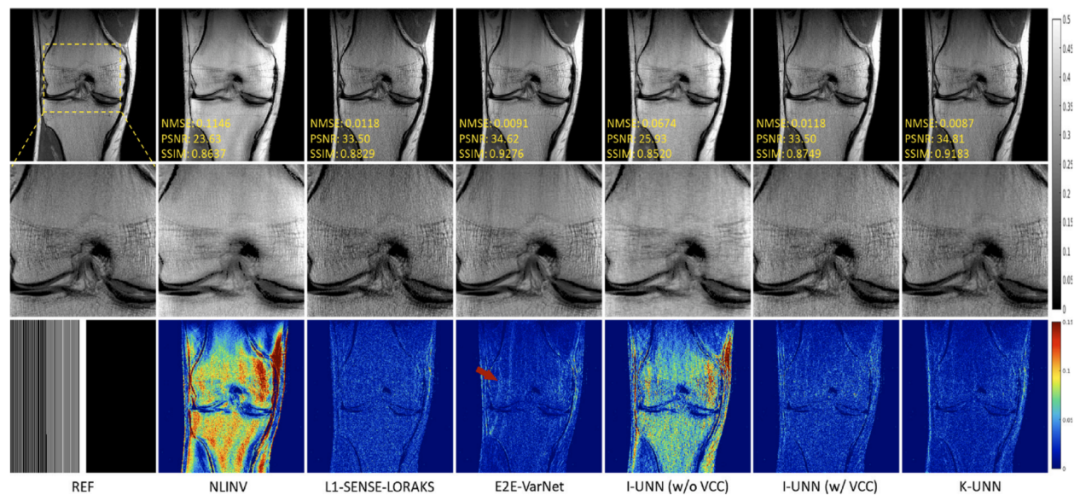

磁共振利用多通道线圈接收人体生理信号,多线圈的数据间具有很强的相关性。团队针对磁共振成像中全采数据难以取得的巨大挑战,提出利用线圈间数据相关性这一物理先验,来构建磁共振物理驱动的无监督深度神经网络成像模型,并分析了网络的误差上界,为成像可靠性给予保障。实验结果(图1)表明,该方法无需训练数据就能够重建出高质量图像,且效果与需要训练数据方法类似。研究成果发表在医学成像领域著名期刊Medical Image Analysis

图1. 5倍加速重建结果